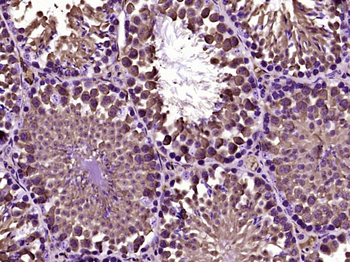

50 μl, 100 μl - MARK3 Recombinant Rabbit Monoclonal Antibody [orb704310]Featured

ICC, IF, IHC-Fr, IHC-P

Human, Mouse

Rat

Rabbit

Recombinant

Unconjugated

50 μl, 100 μl - Featured